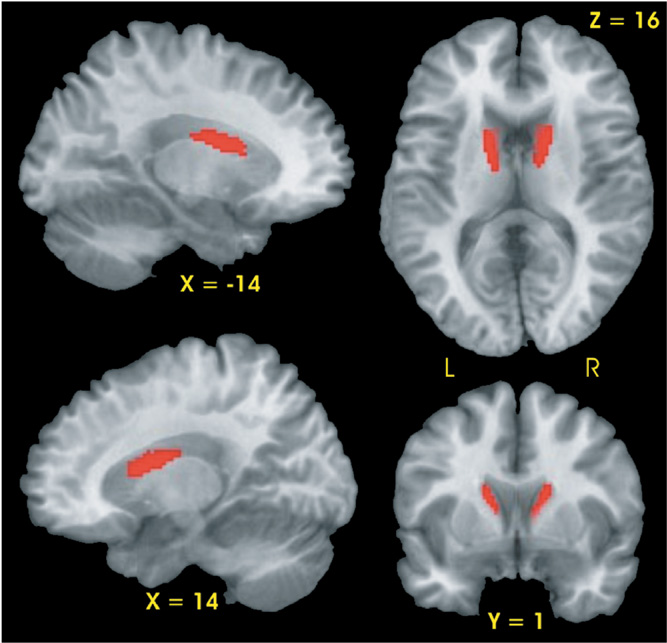

Planned contrasts demonstrated that the CLOSE group had two regions, the right and left head and body of the caudate, with smaller gray matter volumes relative to the CONT group (see Fig. 1). No differences in gray matter volume were observed between the FAR and CONT groups nor between the FAR and CLOSE groups.

Results of voxel-based morphometric analysis. Significantly smaller gray matter volume (red region) was observed in the bilateral caudate of the CLOSE group relative to the Control group.